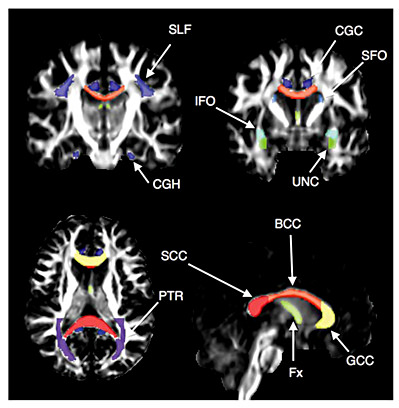

Eleven white matter association area tracts on each side were chosen for analysis (fig. 1), including the uncinate fasciculus, superior longitudinal fasciculus (SLF), superior fronto-occipital fasciculus (SFO), inferior fronto-occipital fasciculus (IFO), posterior thalamic radiation (PTR), and the fornix. The corpus callosum was segmented into three portions: the genu, body, and splenium. The cingulum was segmented into the portion underlying the cingulate cortex and a hippocampal portion. These association tracts were chosen because of literature suggesting their association with the cognitive tests used, or because of their involvement in ALS or FTLD. The corticospinal tract was not included in the analysis, as the changes associated with ALS and PLS diagnoses and motor function have been previously reported for these patients [23].

FA maps with color overlays showing the white matter tracts included in the analysis. Tracts were segmented by atlas analysis. The evaluated tracts were the uncinate fasciculus (UNC), SLF, SFO, IFO, PTR, and the fornix (Fx). The corpus callosum was segmented into three portions: the genu, body, and splenium (GCC, BCC, and SCC). The cingulum was segmented into the portion underlying the cingulate cortex (CGC) and a parahippocampal portion (CGH).